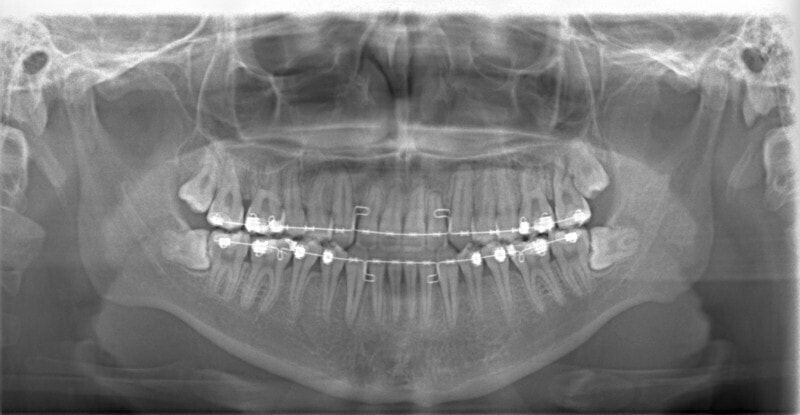

治療中のレントゲンです。

7番、8番の状態や歯根のパラレリング(平行性)をチェックしています。

左上2番の歯根の状態もなんとかもちそうです。

大臼歯は整直されております。

歯根のパラレリングは良好です。

左上2番の歯根も問題なさそうです。

下顎8番は保定期間に入り、しばらくして咬合が安定してから抜歯する予定です。